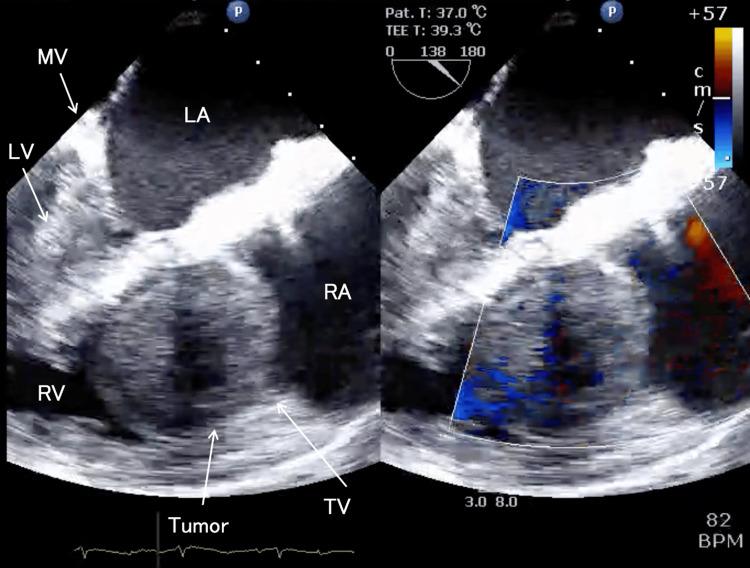

Intravenous leiomyomatosis (IVL) with intracardiac extension can cause circulatory collapse during anesthetic induction due to right heart obstruction. We report the case of a 63-year-old woman with IVL extending into the right ventricle, presenting with right heart failure and shock. To maintain hemodynamic stability and facilitate tumor resection, we established cardiopulmonary bypass (CPB) under local anesthesia before inducing general anesthesia. Preoperative imaging revealed a tumor extending from the right ovarian vein to the right ventricle, causing circulatory failure. In the operating room, CPB was initiated via femoral cannulation under local anesthesia with analgosedation to maintain spontaneous breathing, followed by general anesthesia induction. A median sternotomy was performed, and an additional venous cannula was placed in the superior vena cava to achieve total CPB. The tumor was resected from the right heart and inferior vena cava. The patient was weaned from CPB and ventilation without complications. Pathology was later confirmed to be IVL. She was discharged on postoperative day 30. Establishing CPB before anesthetic induction maintained hemodynamic stability in this patient with IVL, intracardiac extension, and right heart failure, allowing for safe tumor resection.

伴有心内扩展的静脉内平滑肌瘤病(IVL)在麻醉诱导期间可因右心梗阻导致循环衰竭。我们报告一例63岁女性,其IVL延伸至右心室,表现为右心衰竭和休克。为维持血流动力学稳定并便于肿瘤切除,我们在诱导全身麻醉前于局部麻醉下建立了体外循环(CPB)。术前影像学检查显示肿瘤从右卵巢静脉延伸至右心室,导致循环衰竭。在手术室,于局部麻醉下经股动脉插管并给予镇痛镇静以维持自主呼吸后启动CPB,随后进行全身麻醉诱导。行正中胸骨切开术,并在上腔静脉置入另一根静脉插管以实现完全CPB。肿瘤从右心和下腔静脉切除。患者顺利脱离CPB和通气,未出现并发症。病理检查后来证实为IVL。她于术后第30天出院。在麻醉诱导前建立CPB维持了该患有IVL、心内扩展和右心衰竭患者的血流动力学稳定,从而得以安全地切除肿瘤。